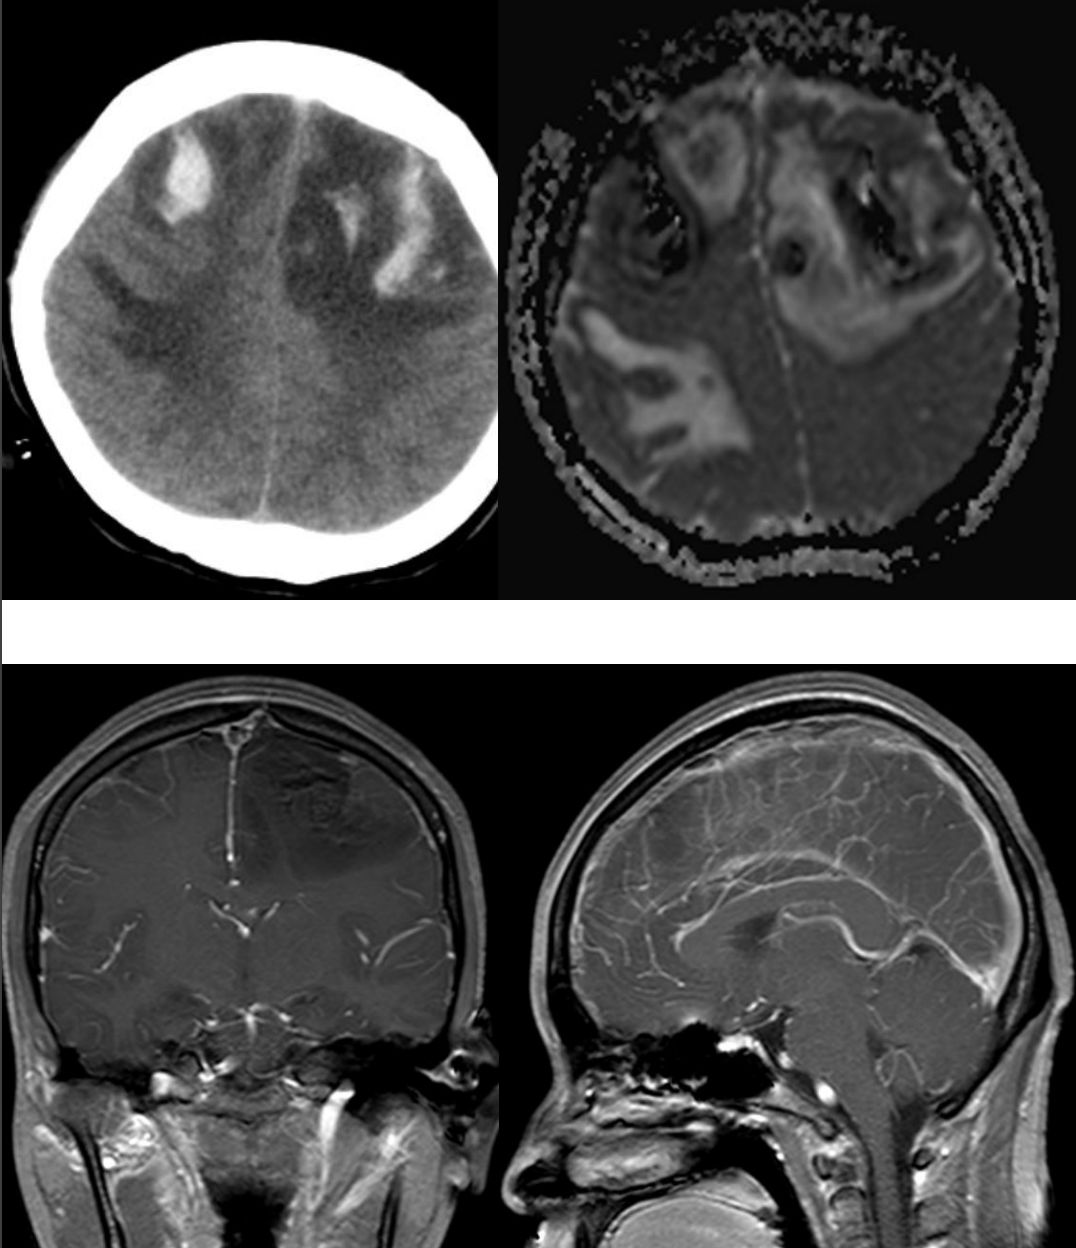

61岁,男性,右腿间歇性无力,轻度头痛(全脑),进行性认知功能障碍和嗜睡;血液及脑脊液检查无感染证据,无肿瘤细胞。

答案:巨大动脉瘤伴瘤内完全血栓形成。

本病例较难,在文献中也是通过手术才得到确诊。东非逗留个人史+脑脊液囊虫抗体滴度(1:20)最初诊断考虑脑囊虫病。术中诊断:左侧大脑前动脉巨大动脉瘤伴瘤内完全血栓形成,伴载瘤动脉血栓形成(原因可能为部分血栓形成的动脉瘤不断增长或血栓的逆行扩散而使母血管受压)回顾分析:MRI双侧额叶巨大肿块,T1WI病灶新月形高信号;T2WI病灶内无血管流空影,灶周水肿;CT平扫高密度肿块伴部分壁钙化伴少许瘤内出血;注射对⽐剂后未见明显强化(载瘤动脉血栓形成导致造影剂无法进入)导致误诊的主要原因。

巨大颅内动脉瘤(giant intracranial aneurysm)生长过程:自发性血栓形成→缓慢生长形成占位效应,破裂形成SAH。巨大动脉瘤腔内完全血栓形成事实上非常罕见。颅内动脉瘤伴血栓形成CT特征是环状强化,囊壁环状钙化,管腔内混杂高密度,可见靶征。MRI特征包括“洋葱皮征”,肿块内血管流空影,T2WI的瘤周水肿,病灶明显强化。总而言之,首先颅内球形肿块伴病灶内出血和壁钙化,鉴别诊断需考虑完全血栓形成的GIA;其次颅内球型肿块未出血、未钙化需鉴别颅内巨动脉瘤。